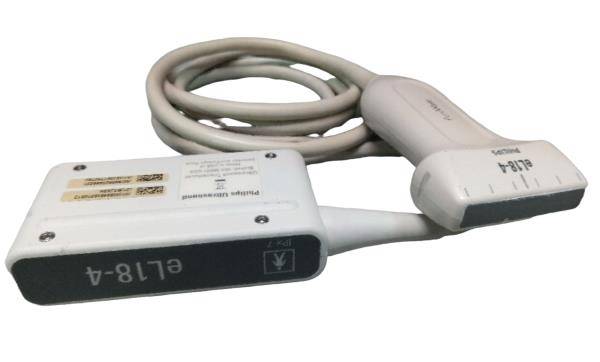

Probe Function: 3.5MHZ convex, abdominal organs

The Ultrasound Scanner is a state-of-the-art device designed for comprehensive pregnancy imaging. It features both convex and transvaginal probes, allowing healthcare professionals to obtain detailed images of the fetus and surrounding structures. This dual-probe system enhances diagnostic accuracy, making it easier to monitor the health of the unborn child. Expecting mothers benefit from these advanced imaging techniques, enabling early detection of potential complications.